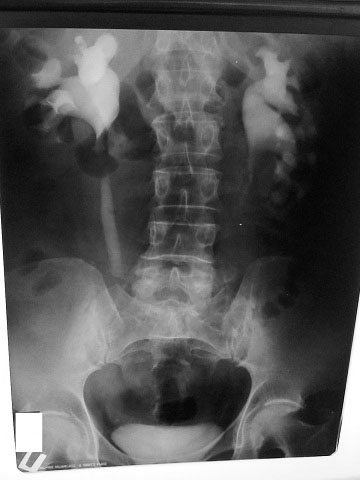

Рентгенолог сказал, что есть сдавление правого мочеточника извне на уровне с\3. Снимки не видела. Думаю, после обеда смогу их увидеть и выложить. Хочу её после обеда, как освободится аппарат, пересмотреть.

средней трети мочеточника

Сори за задержку- технические трудности.

Вот снимки: